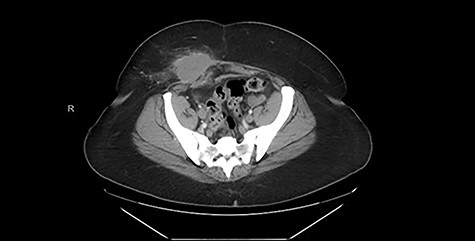

Computed tomography (CT) scan of the abdomen and pelvis with contrast revealed a high-density soft tissue opacity measuring 5.8 cm × 4.4 cm in the subcutaneous tissue of the right lower quadrant abutting the anterior aspect of the abdominal wall and associated moderate surrounding subcutaneous soft tissue stranding. These findings were suggestive of a high-density seroma versus post-surgical hematoma. Figure 1 displays the pertinent CT images from admission.

CT (axial view) demonstrating high-density soft tissue opacity measuring 5.8 × 4.4 cm in the subcutaneous tissue of the right lower quadrant abutting the anterior aspect of the abdominal wall.